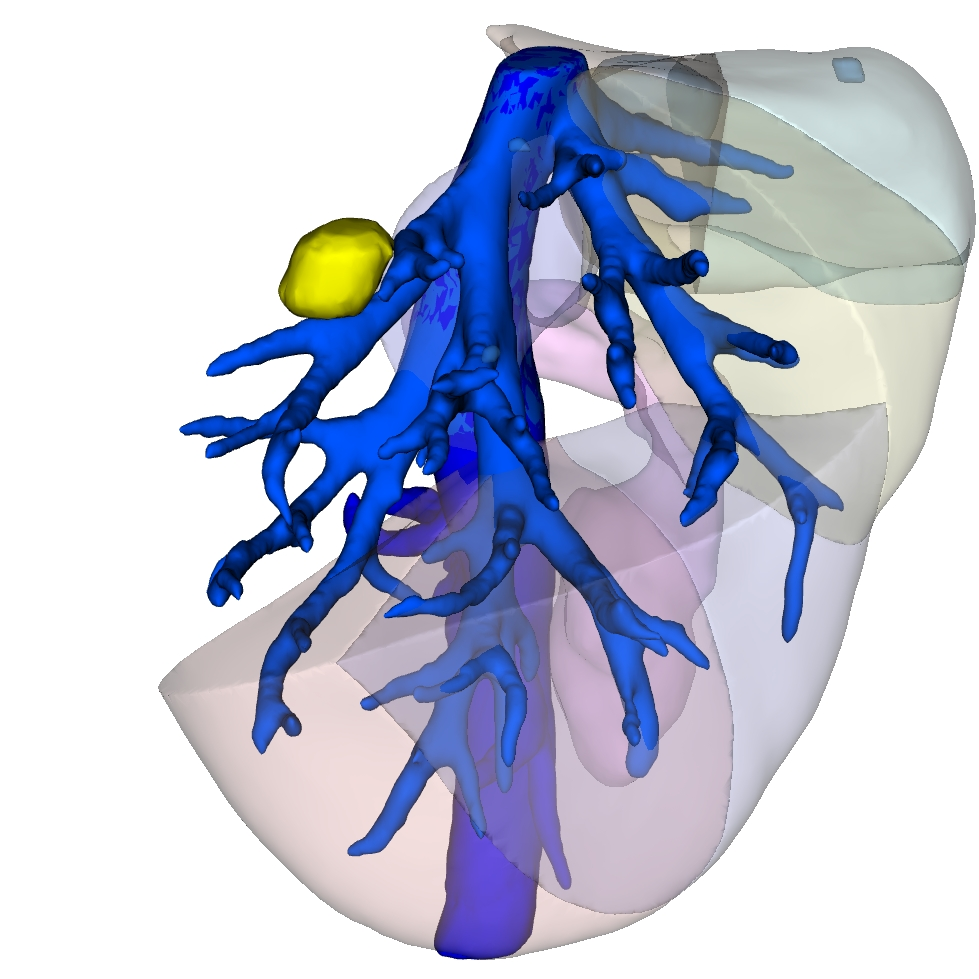

肝癌专病中心MDT于2025年9月正式启动,运行半年来严格落实常态化诊疗机制,成效显著。中心坚持每周2次规范化多学科讨论,打破科室诊疗壁垒,汇聚肝胆、消化、肿瘤、影像、病理、肝病等多学科精锐力量,聚焦各类肝癌的精准诊疗需求。截至目前,已为40余例肝恶性肿瘤患者开展MDT联合诊疗,量身定制手术切除、介入治疗、靶免联合等个性化诊疗方案;2025年肝胆诊疗中心完成100余例肝脏手术,涵盖高难度精准肝切除、腹腔镜及机器人肝切除、5G远程机器人手术,以硬核技术提升诊疗效果,赢得患者及家属广泛认可。